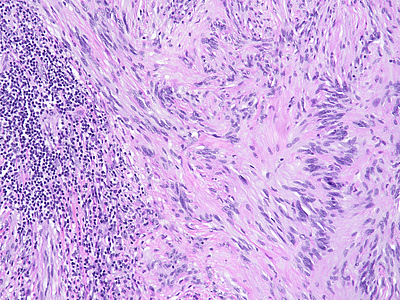

During laparoscopic surgery, the tumour proved to be confined to the appendix, with no other intra-abdominal findings (Panel A). The resection specimen disclosed a well circumscribed solid tumour, 4.2 cm in maximum diameter, with a homogeneously yellowish-white cut surface (Panels B and C).  Histologically, we observed a loose to densely cellular, spindled-cell neoplasia, arranged in fascicular and sweeping patterns (Panel D). Lymphoid aggregates, sometimes forming lymphoid follicles with germinal centres, were  found distributed at the periphery and also throughout the tumour (Panels E and F). The neoplastic cells had sparse cytoplasm and elongated, bland nuclei with inconspicuous nucleoli; focal and moderate atypia was noted (Panel G). Mitotic activity was <5mitoses/10HPF. Haemorrhage or necrosis were not observed. Upon immunohistochemistry, there was diffuse and strong positivity for S100 protein (Panel H) and moderate positivity for GFAP (Panel I). CD117 marked intralesional mast cells, whereas the tumour cells were negative (Panel J). Desmin and smooth muscle actin were negative (not shown).

The characteristic morphology directs to the correct diagnosis: a well-circumscribed lesion, with a marbled appearance due to densely cellular areas alternating with densely cellular areas; and neoplastic spindled cells, sometimes with focal, degenerative atypia. Lymphoid cuffs, usually present in soft tissue schwannomas, have an unclear aetiology; in the appendix, its presence probably is due to remnants of local MALT-tissue. Long fascicular pattern, an epithelioid appearance, tumoral necrosis and increased mitotic activity must raise concern for malignant transformation to MPNST.